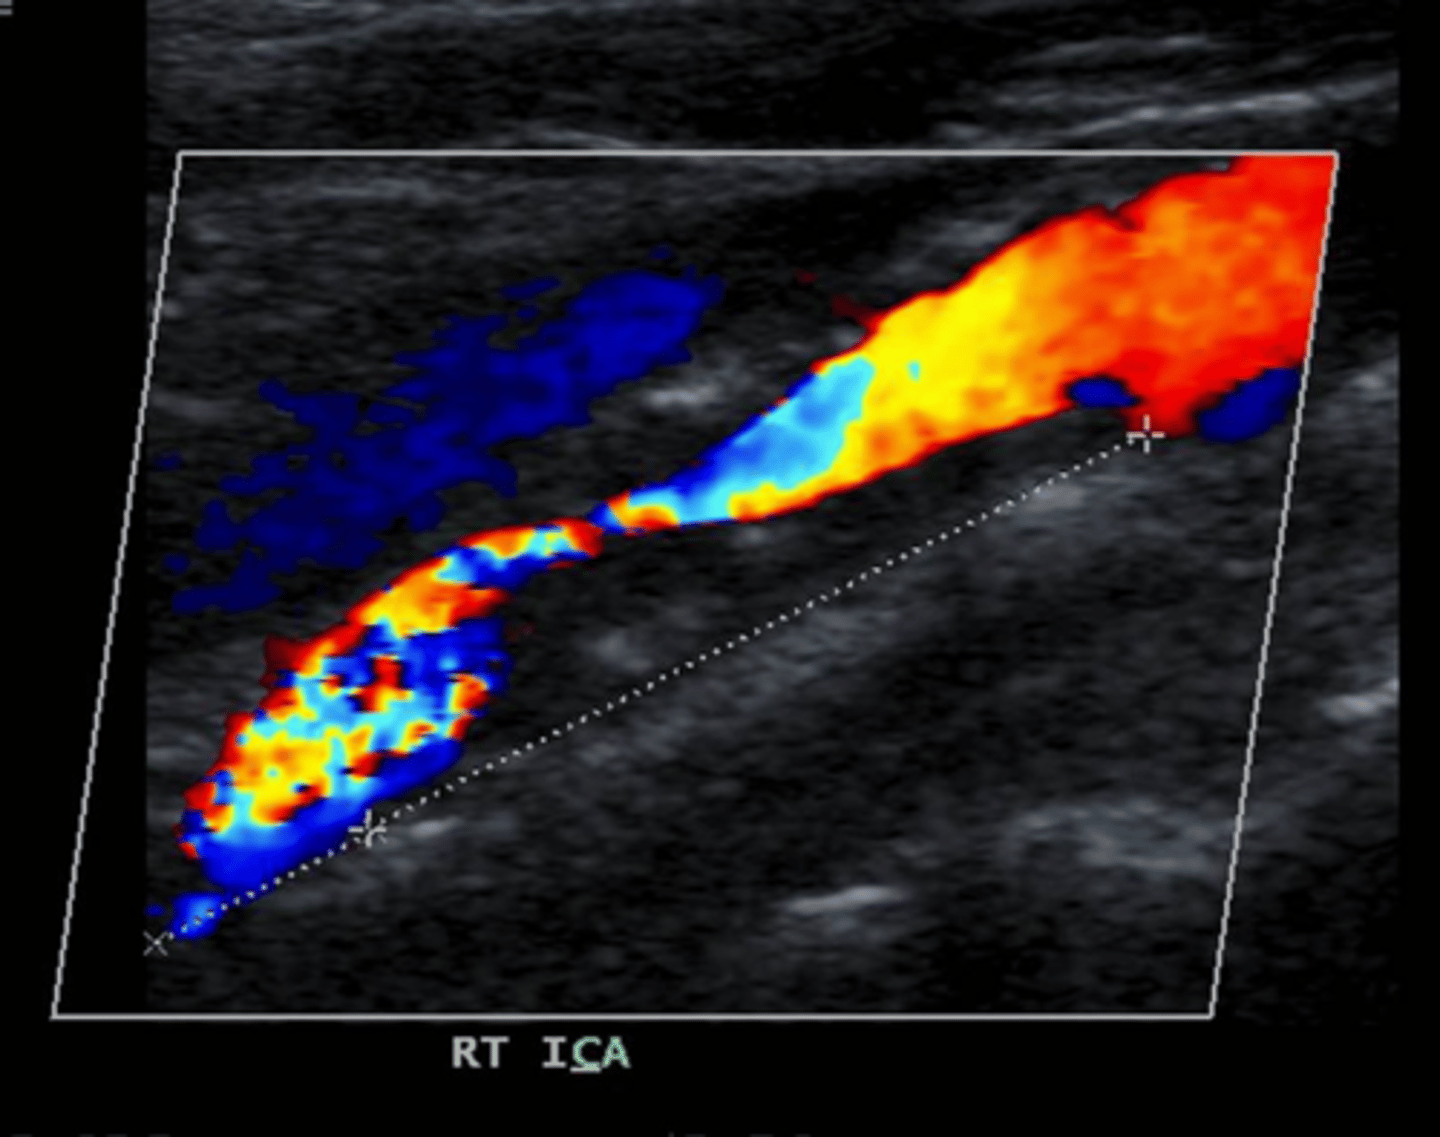

Sample was not obtained at maximum stenosis.

In this example, the ICA velocities may underestimate the category of stenosis. Why?

<p>In this example, the ICA velocities may underestimate the category of stenosis. Why?</p>